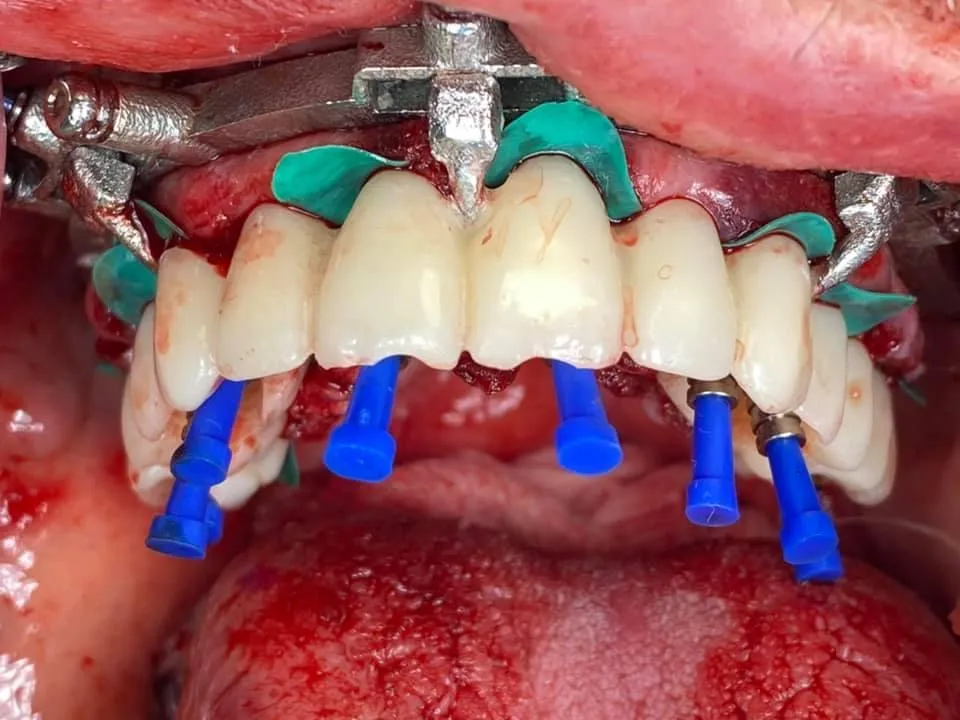

The Ultimate All on X ONLINE

✅Step by Step Program

✅Learn how to perform full arch treatment both non-guided & guided